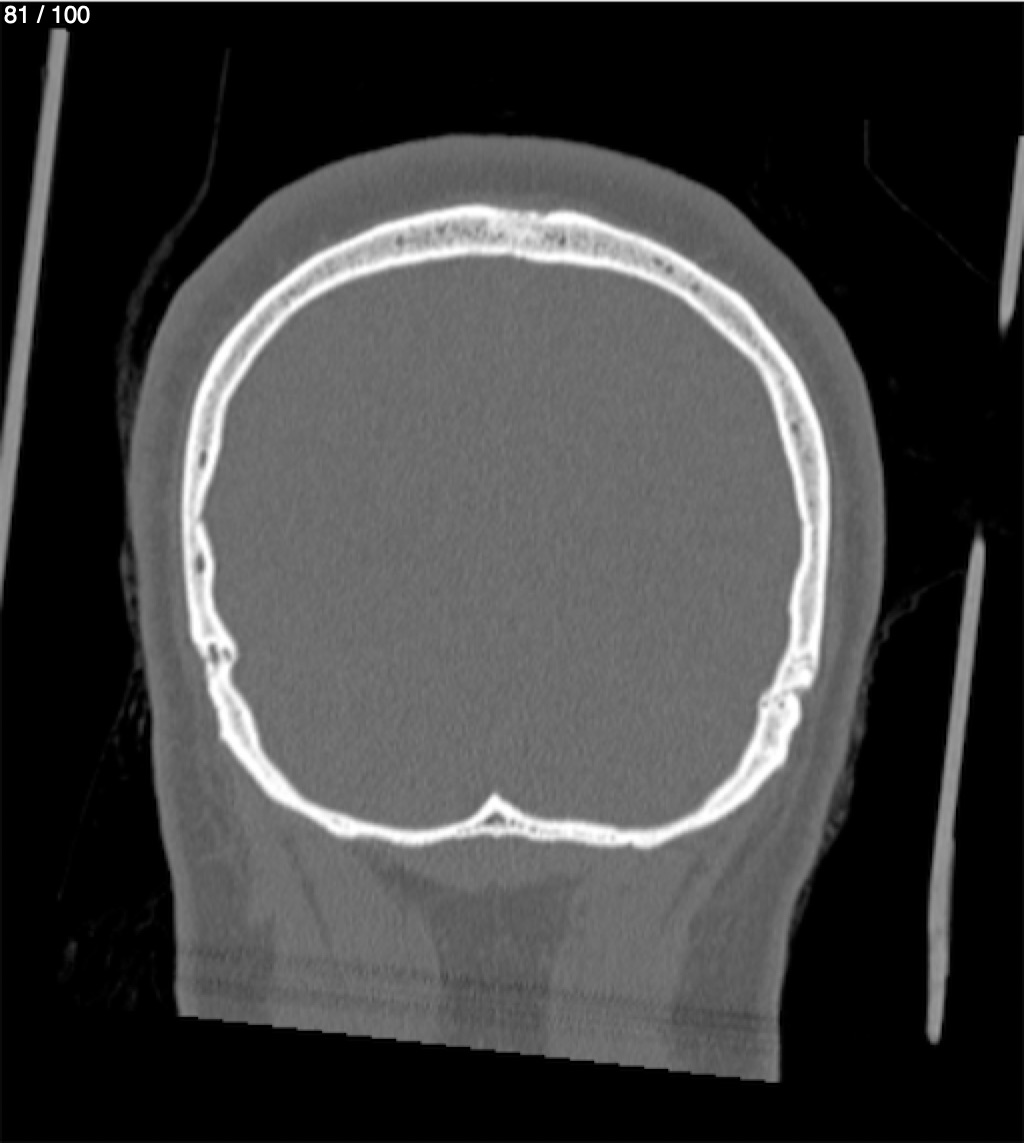

Reybet Garcia Fuentes 30A - T.C Craneo